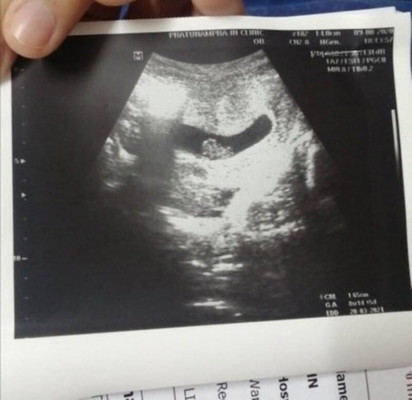

วันนี้หมอบอกว่าแม่มีพาหะธารัสซีเมีย อยากทราบว่ามีแม่ๆ ท่านใหนเป็นพาหะเหมือนกันรึเปล่าคะ ขอคำแนะนำหน่อยค่ะ มีผลอะไรกับลูกรึเปล่า 8 Week แล้วค่ะ ขอบคุณค่ะ 🙏🙏🙏

หมอก็บอกเหมือนกันค่ะ ตอน 8 สป แต่ว่าก็ไม่ได้บอกอะไรอีก ตั้งครรภ์พบหมอปกติค่ะแม่